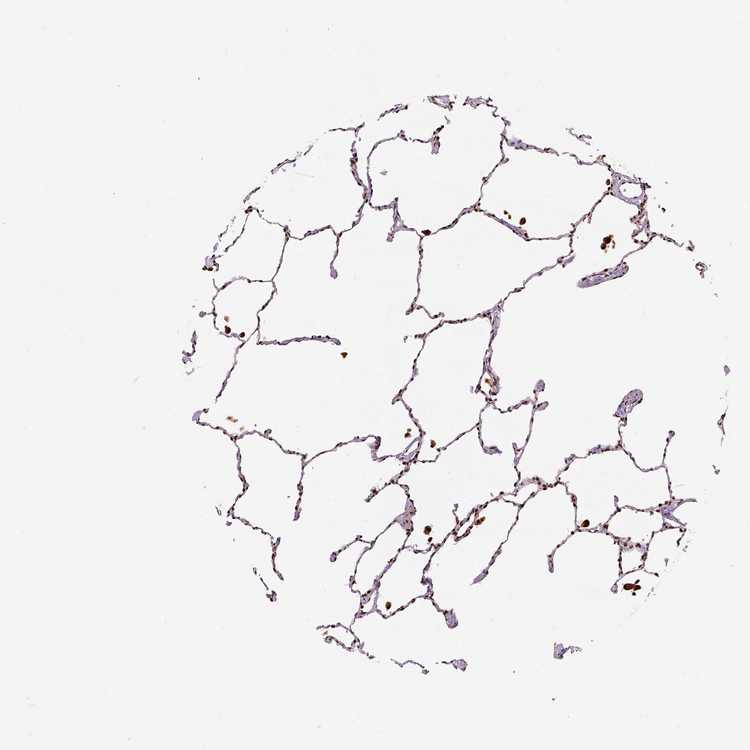

LUNG - Antibody stainingi

Antibody staining in the annotated cell types in the current human tissue is reported as not detected, low, medium, or high, based on conventional immunohistochemistry profiling in selected tissues. This score is based on the combination of the staining intensity and fraction of stained cells.

Each image is clickable and will lead to virtual microscopy that enables deeper exploration of all samples and also displays staining intensity scores, fraction scores and subcellular localization as well as patient and tissue information for each sample.

Antibody HPA021238Antibody HPA062245Antibody CAB069927

Alveolar cells High-High

Alveolar cells type I -Medium-

Alveolar cells type II -Medium-

Endothelial cells -Medium-

Macrophages HighMediumHigh